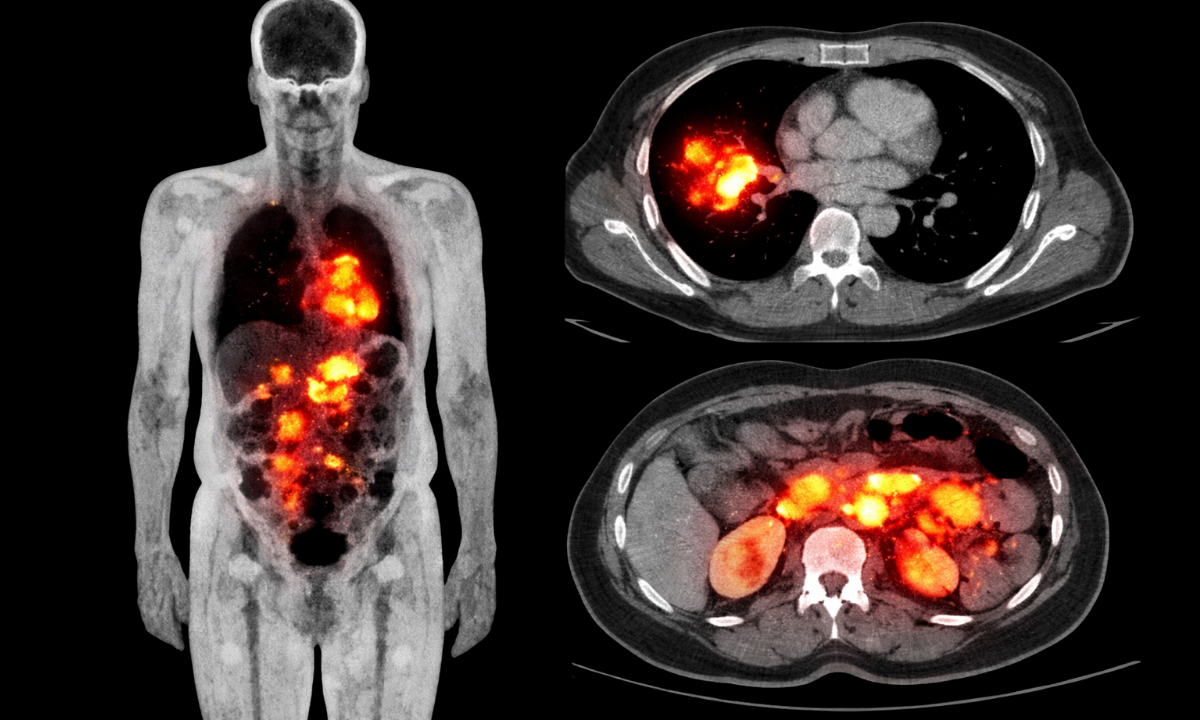

A PET scan (Positron Emission Tomography) is a broad, powerful imaging tool used in oncology, cardiology, and neurology. A DOTA PET scan, on the other hand, is a specialized form of PET imaging, designed primarily for neuroendocrine tumors (NETs).

A PET scan works by detecting metabolic activity in the body. Cancer cells, for example, consume more glucose than normal cells. By injecting a radioactive tracer (commonly FDG), we can see areas of abnormally high metabolic activity.

A DOTA PET scan is a targeted scan. Instead of looking at glucose metabolism, it detects somatostatin receptors, which are commonly found on neuroendocrine tumor cells.

Neuroendocrine tumors are notoriously slow-growing and often missed on conventional imaging. In many of my patients, standard PET scans appear “normal”, while a DOTATOC PET scan reveals widespread disease.